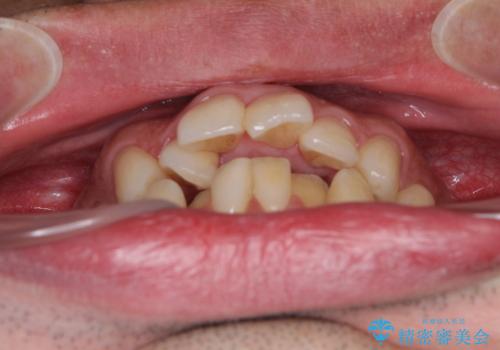

下顎骨が顕著な左右差を持って成長したため、右側にずれている状態でした。

この方は元々骨格的な偏位が大きかったためか、治療中に下顎骨が上顎骨よりも右外側に誘導されて、右側の奥歯が全く咬合しない状態が続いてしまいました。